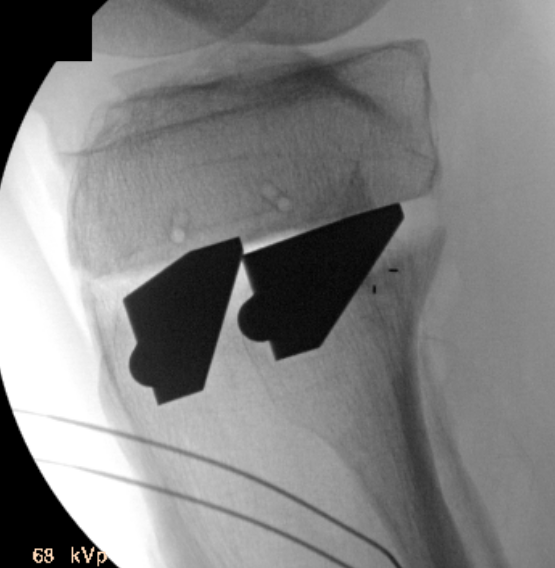

Opening of wedge

- slow

- stacked osteotomes / lamina spreader / wedged osteotomes

- ensure no change of posterior slope on lateral

Arthrex wedged osteotomes

Opening osteotomy with laminar spreader